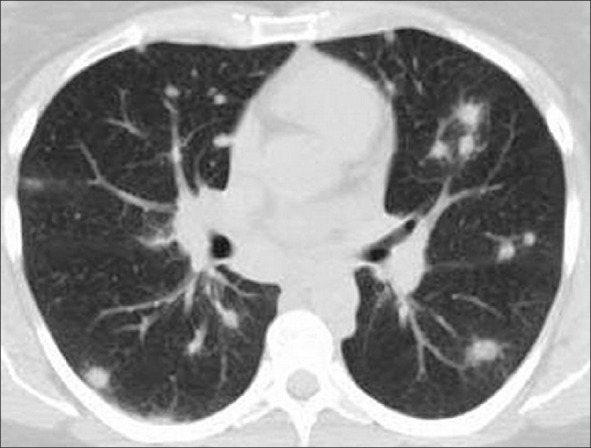

Chest X-ray and chest computed tomography (CT) confirmed the presence of bilateral pulmonary nodules [Figure 2]. As multiple metastases due to tumor of unknown origin were suspected, the patient underwent a series of diagnostic tests: brain and abdomen CTs, gastroscopy, colonoscopy, bronchoscopy, mammography, thyroid ultrasound and skeletal scintigraphy, none of which indicated primary extrapulmonary tumor. The patient underwent video-assisted thoracoscopy and multiple lung biopsies were performed. Histopathology and immunohistochemical examination of the specimens showed pulmonary parenchyma with focuses of sarcoma. A metastatic malignant smooth muscle cells neoplasm with uterine origin was diagnosed [Figure 3]. Cell nuclei presented diffuse moderate mitotic activity (6 MF/10 HPF), but there were also some atypical mitoses. The immunohistochemical examination revealed that the tumor was positive in Desmin and smooth muscle actin (SMA) and negative in CD117 and CD34. Pleural fluid was also found positive for metastatic malignancy. Both pathology and cytopathology reports excluded that the condition was associated with benign metastasizing leiomyoma.

| Fig. 2 Chest computed tomography was consistent with multiple pulmonary nodules and pleural effusion